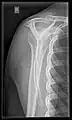

Y-projection

The lateral contour of the shoulder should be positioned in front of the film in a way that the longitudinal axis of the scapula continues parallel to the path of the rays. This method reveals:[24]

• The horizontal centralization of the humerus head and socket

• The osseous margins of the coraco-acromial arch and hence the supraspinatus outlet canal

• The shape of the acromion

This projection has a low tolerance for errors and, accordingly, needs proper execution.[24] The Y-projection can be traced back to Wijnblath’s 1933 published cavitas-en-face projection.[25]